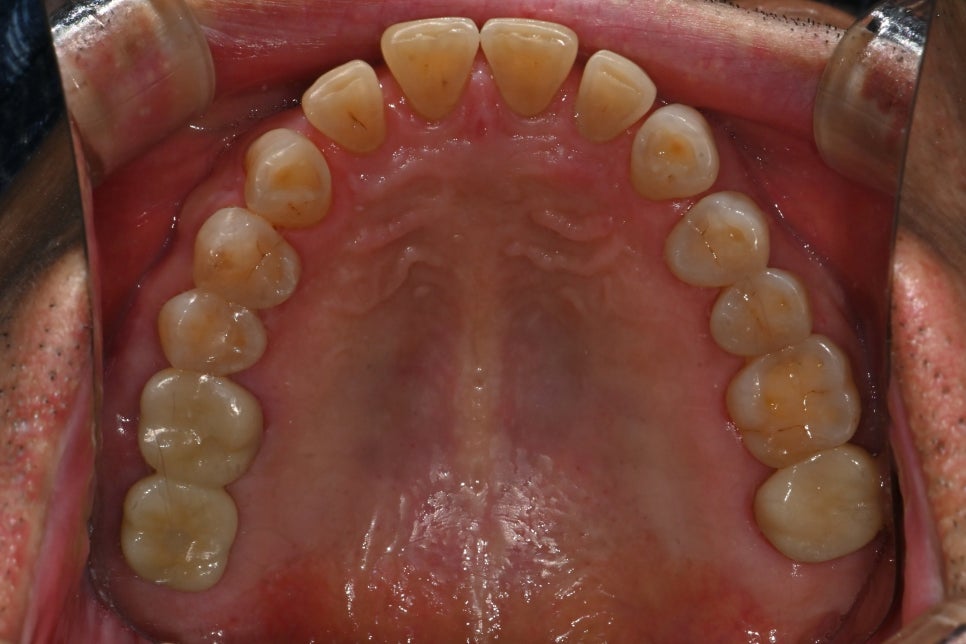

치료 후 변화

완성 후 환자분이 가장 먼저 말씀하신 것은

“씹는 게 편해졌다”는 점이었습니다.

오래 비워졌던 어금니가 제 기능을 찾으면

자연스럽게 턱의 균형이 잡히고,

음식의 질감도 훨씬 선명하게 느껴집니다.

또한 통증 걱정 없이 드실 수 있다는 점에서

생활의 질이 확실히 좋아집니다.

정기 검진 내원 시에도 잇몸과 임플란트 주변이

잘 유지되고 있었고, 관리 방법(치실·치간칫솔 사용)만

꾸준히 안내해 드렸습니다.